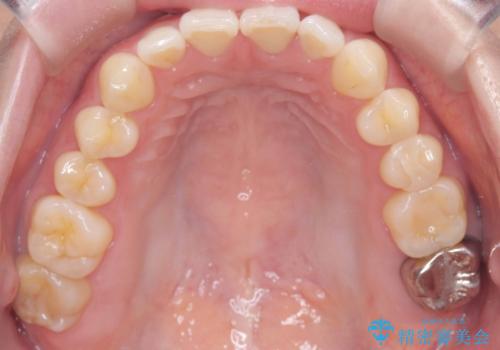

すきっ歯・切端咬合・空隙歯列|インビザラインで11ヵ月で治療完了

- すきっ歯と切端咬合(上下の前歯が先端で当たるかみ合わせ)を主訴にご来院された患者様です。

矯正検査を行った結果、非抜歯でインビザラインによる治療が可能と判断し、マウスピース矯正で改善を行いました。

11ヵ月で矯正治療が終了し、前歯の隙間も改善、見た目とかみ合わせも良好な状態となり、患者様にも大変ご満足いただけました。